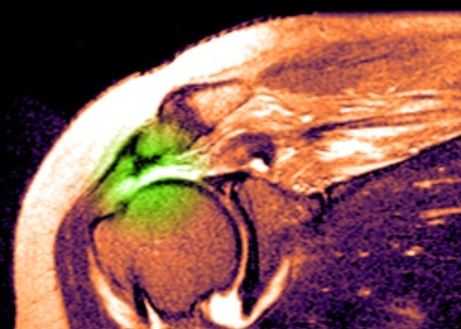

МРТ плечевого сустава. Т2-взвешенная корональная МРТ. Разрыв вращательной манжеты. Цветовая обработка изображения.

Краткие сведения по анатомии плечевого сустава

При МРТ плечевого сустава косвенным признаком разрыва вращательной манжеты служит высокий сигнал на Т2-взвешенных от поверхности сустава до субакромиальной (субдельтовидной) сумки. Частичные разрывы чаще всего по передней поверхности сухожилия м.supraspinatus, реже примыкая к большой бугристости или сухожилия м. infraspinatus.